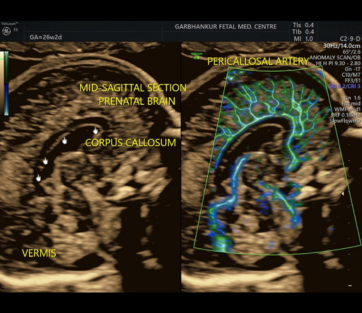

Neurosonogram

A neurosonogram, also known as a neonatal neurosonogram or neonatal cranial ultrasound, is a specialized ultrasound examination that focuses on imaging the brain structures of newborns

- Ultrasound Probe

- Imaging

- Evaluation

- Follow-Up and Monitoring

- Consultation